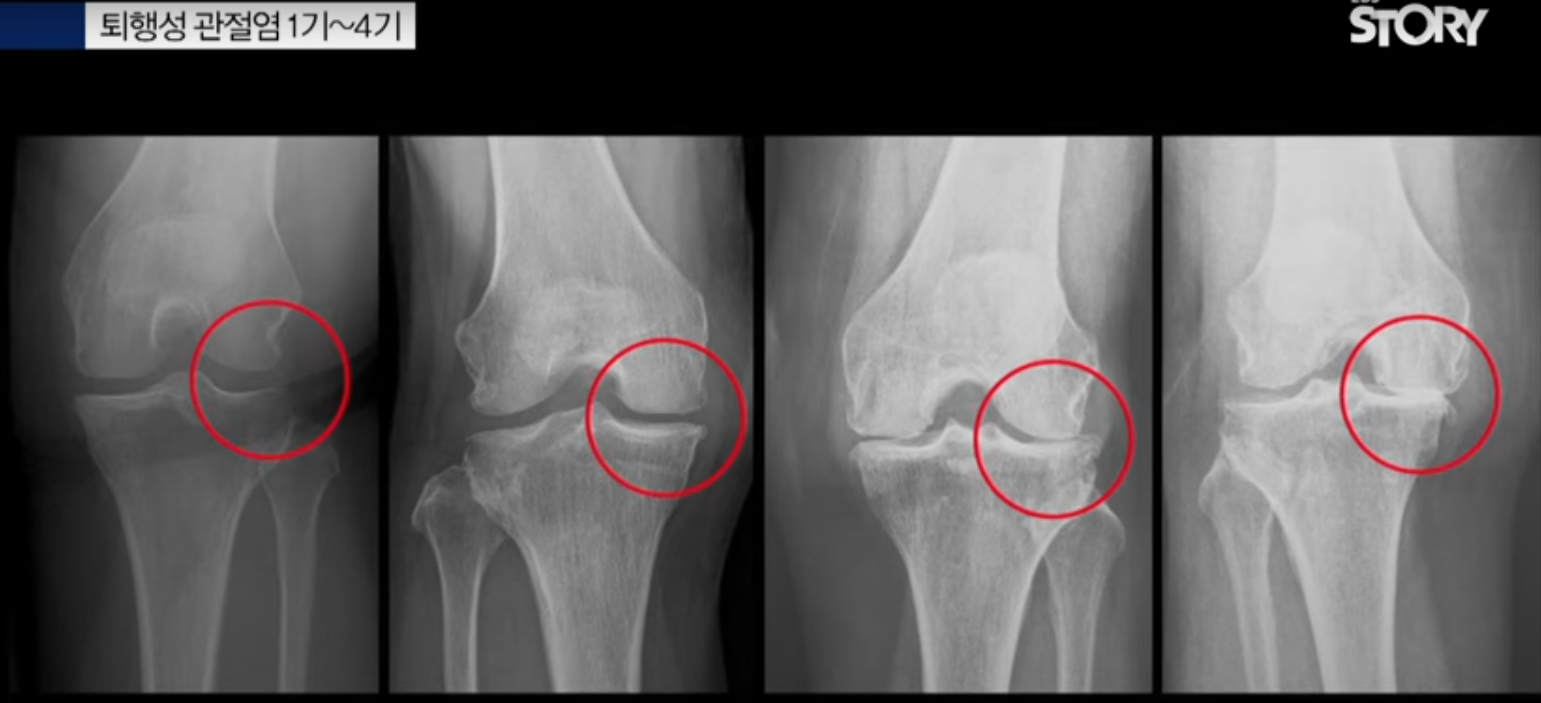

퇴행성 관절염 진행단계

퇴행성 관절염의 진행 단계는 일반적으로 4단계로 구분됩니다:

1단계 (초기)

- 약 10%의 연골이 감소된 상태

- 간헐적인 통증 발생

- 미세한 골극 형성, 정상적인 관절 간격 유지

- 보존적 치료가 가능한 단계

2단계 (경도)

- 연골 손상으로 관절 간격이 좁아지기 시작

- 관절 표면이 울퉁불퉁해짐

- 골극 형성이 뚜렷해짐

- 염증과 통증이 나타남

3단계 (중등도)

- 연골이 더 많이 닳아 뼈가 서로 닿기 시작

- 다발성 골극 형성

- 관절 간격이 중등도로 감소

- 움직일 때마다 통증 발생

4단계 (말기)

- 연골이 거의 또는 완전히 소실됨

- 뼈와 뼈가 직접 부딪힘

- 심한 골극 형성과 심각한 관절 간격 감소

- 관절이 뻣뻣해지고 부어올라 일상생활이 어려워짐

이러한 단계 구분은 주로 엑스레이 검사를 통해 이루어지며, 켈그렌-로렌스 분류법(K-LG)이라고 합니다. 단, 방사선학적 변화가 반드시 증상의 심각도와 일치하지는 않으므로, 개인별로 증상과 기능 저하 정도를 종합적으로 평가해야 합니다